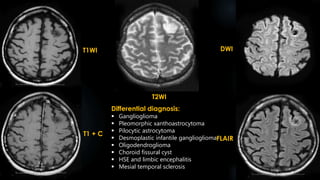

T1WI

T2WI

FLAIR T1 + C

Differential diagnosis:

sPNET

ATRT

Choroid plexus carcinoma

Intracranial lipoma

Intracranial dermoid

Craniopharyngioma